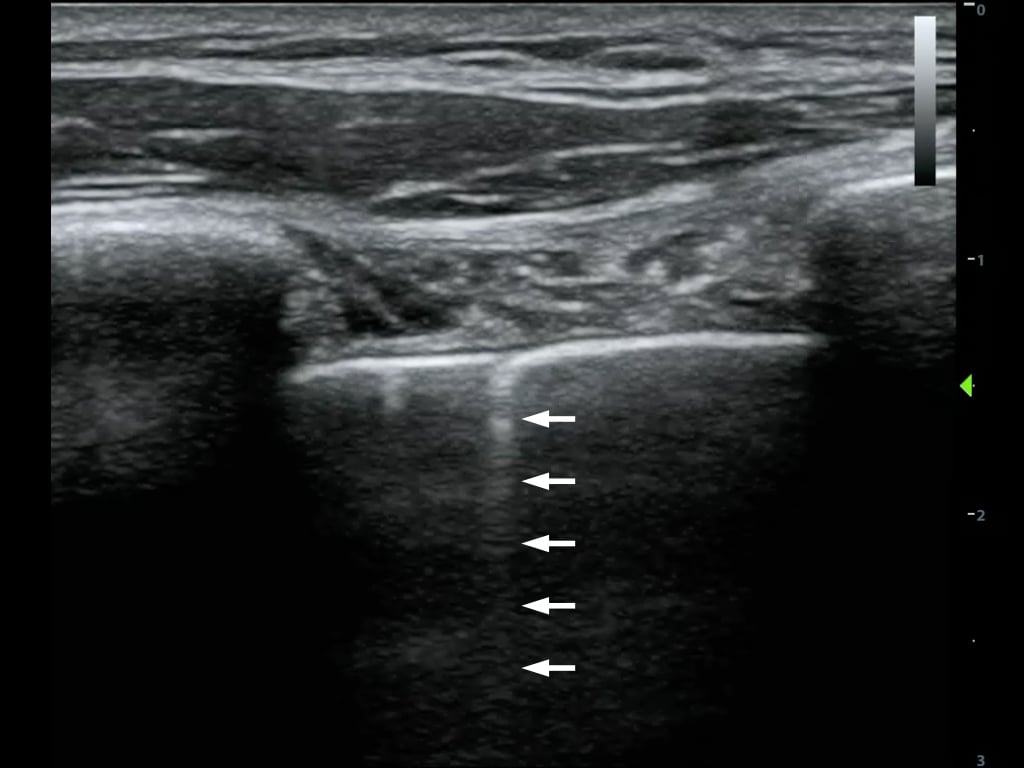

- Shadowing is caused by partial or total reflection or absorption of the sound energy

- A much weaker signal returns from behind a strong reflector (air) or sound-absorbing structure (gallstone, kidney stone, bone) (Figure 7)

- Figure 7. Shadowing from gallstones and edge artifact at lateral wall of gallbladder

- Edge Shadowing Artifact is a thin acoustic shadow behind lateral edges of cystic structures

- Sound waves encountering a cystic wall or a curved surface at a tangential angle are refracted with few echoes returning to the transducer (Figure 7)